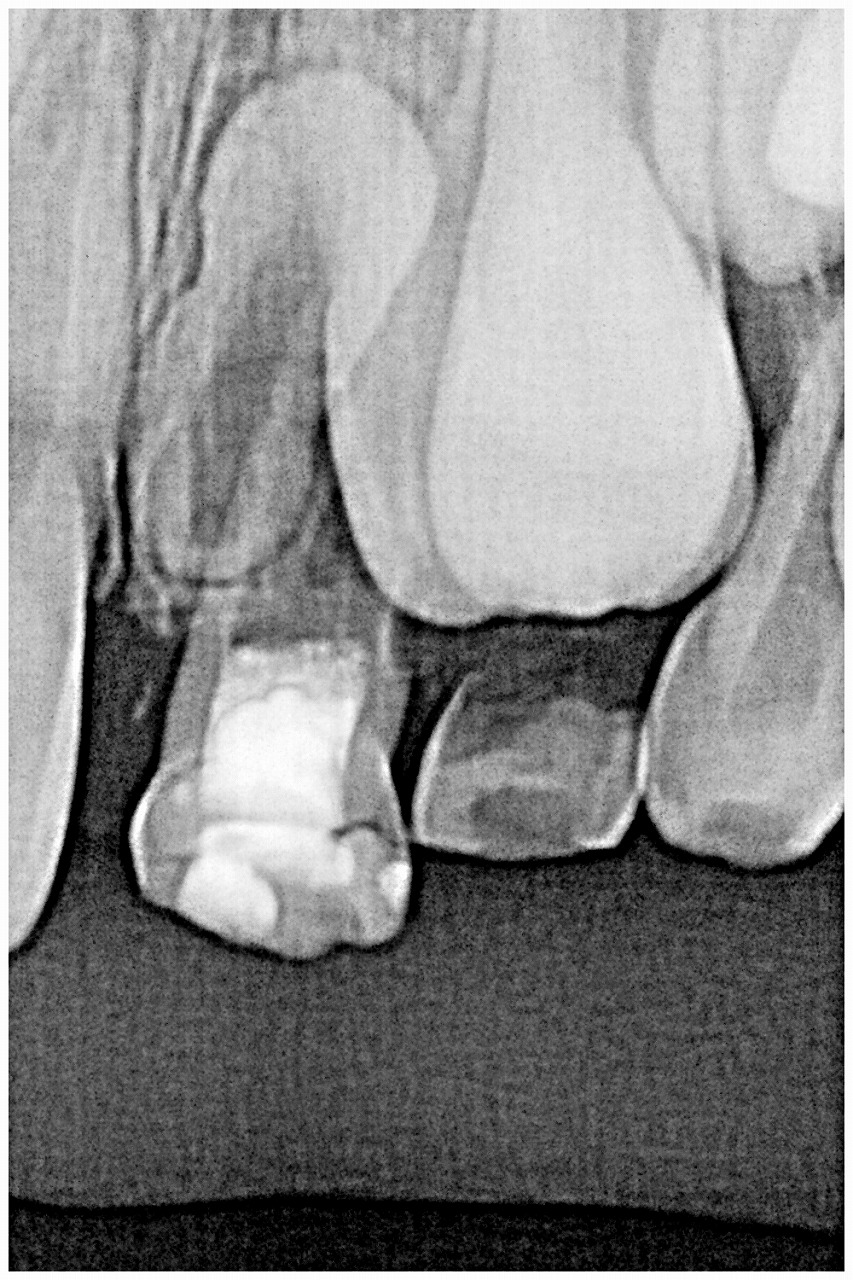

過剰歯が存在しており、右は永久歯が2本生えてきているにもかかわらず、左はまだ2本とも乳歯のまま 心配になり精査のために歯科へ

乳歯がまだ抜けずにいます

なぜ永久歯が生えてこないのでしょう?

埋伏した逆性の過剰歯が場所を取り邪魔をしています

乳歯2本と過剰歯の抜歯を抜かなければ永久歯が出てこないとお話しました